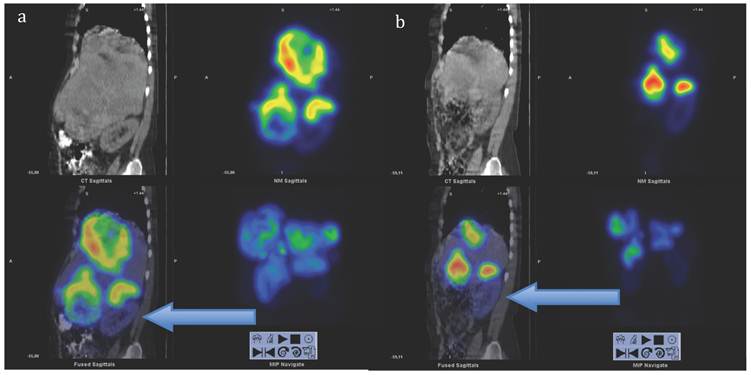

Figure 9

SPECT-CT images (left) and corresponding diagnostic CT (right) of largest liver metastasis in the left liver lobe at time of dosimetry at cycle 1, 3 and 6 (top to bottom). SPECT-CT images: left upper corner attenuation correction CT, right upper corner attenuation corrected SPECT, left lower corner fused SPECT-CT (all transversal views), right lower corner maximum intensity projection (MIP). Note the concentric shrinkage of the tumour and the increasing homogeneity of the uptake distribution.

Applying the same method as previously described for solid organs to the tumours [12], all measured tumours increased their activity concentration and, as a consequence, the absorbed dose throughout the course of therapy. Figure 7, 8 and 9 show the calculated doses for the largest metastases in the liver, one in each lobe, at cycle 1, 3 and 6. The areas that were chosen represented the highest uptake at cycle 1. The activity distribution grows more homogeneous during the treatment, while the tumour appears to shrink concentrically according to the fused SPECT-CT images. This implies an even more pronounced increase of uptake in tumour areas outside those areas that are shown here. The more homogeneous activity distribution in the remainder of the large liver metastases is obvious in Figure 6.

Figure 4 demonstrates the growth of the largest metastasis in the liver representing the main total tumour burden, measured according to RECIST in contrast enhanced CT images. Combined chemotherapy managed to decrease only slightly the diameter of a pelvic tumour, while all other metastases continued to grow in size. After the initiation of PRRT, all metastases decreased on treatment with 177Lu-DOTA-octreotate and continued to do so at subsequent times of evaluation. Three months after cycle 7, all liver metastases showed radiological signs of necrosis. The sum of the tumour diameters decreased by 44% according to RECIST since the start of PRRT, corresponding to a partial remission. Also according to the scintigraphy acquired during each cycle, the total tumour burden continued to decrease throughout the whole therapy (Figure 5, whole body scans at 24 hrs after infusion, cycle 1 to 7; upper row anterior views, lower row posterior views). Figure 6 illustrates the volume reduction of the liver along with the tumour burden on sagittal views at start of PRRT and during the final treatment cycle. The right kidney, dislocated at start of PRRT, had returned back to its normal anatomical place by cycle 7 (arrow).